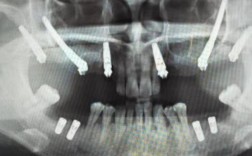

种植体失败(最严重的“后遗症”)

- 表现: 种植体在骨整合期(通常3-6个月)失败(未与骨结合),或在功能使用期后期松动、脱落。

- 原因:

- 骨整合失败: 术中创伤过大、感染、骨量严重不足未处理、患者全身状况差(如严重糖尿病、骨质疏松、长期服用免疫抑制剂/双膦酸盐类药物等)、吸烟、不良修复体设计导致应力集中等。

- 后期失败: 种植体周围炎、咬合力过大/创伤、种植体/基台/牙冠材料或连接方式问题等。

- 处理: 失败的种植体需要手术取出,待骨愈合后,评估条件是否可以重新植入种植体,或选择其他修复方式(如固定桥、活动义齿)。

- 长期影响: 缺失牙齿未修复,可能影响邻牙倾斜、对颌牙伸长、咀嚼功能下降、发音问题、美观问题等,重新种植可能需要额外的手术和费用。

- 全面的术前评估: 包括详细的口腔检查、CBCT影像学检查(精确评估骨量、神经血管位置)、全身健康状况评估(如血糖、血压、凝血功能、用药史等)、吸烟史评估。